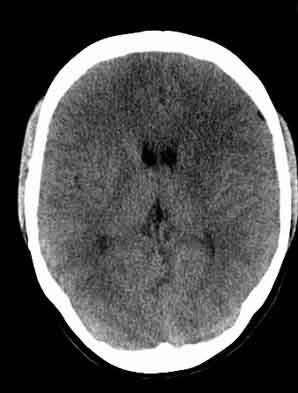

患者,女,29,头痛呕吐2月余,已建议增强或mri进检。

额叶脑白质象是有问题

额叶低密度影,建议增强。

脑沟裂消失,脑白质密度似有减低,考虑脑炎。

左额叶白质密度减低,考虑脑炎,建议增强或mri .

大脑表面脑沟裂消失,颅压高的表现,经常遇到这样的现象,都没有一个明确的结论,望高人指点。

额叶密度减低好像伪影。

双侧脑室前角、旁周围白质低密度减低,边界模糊不清,患者女性:大胆推测,脑白质脱髓鞘改变。mri检查